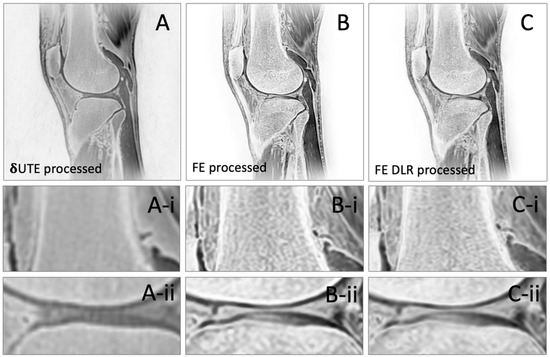

Bone Imaging of the Knee Using Short-Interval Delta Ultrashort Echo Time and Field Echo Imaging